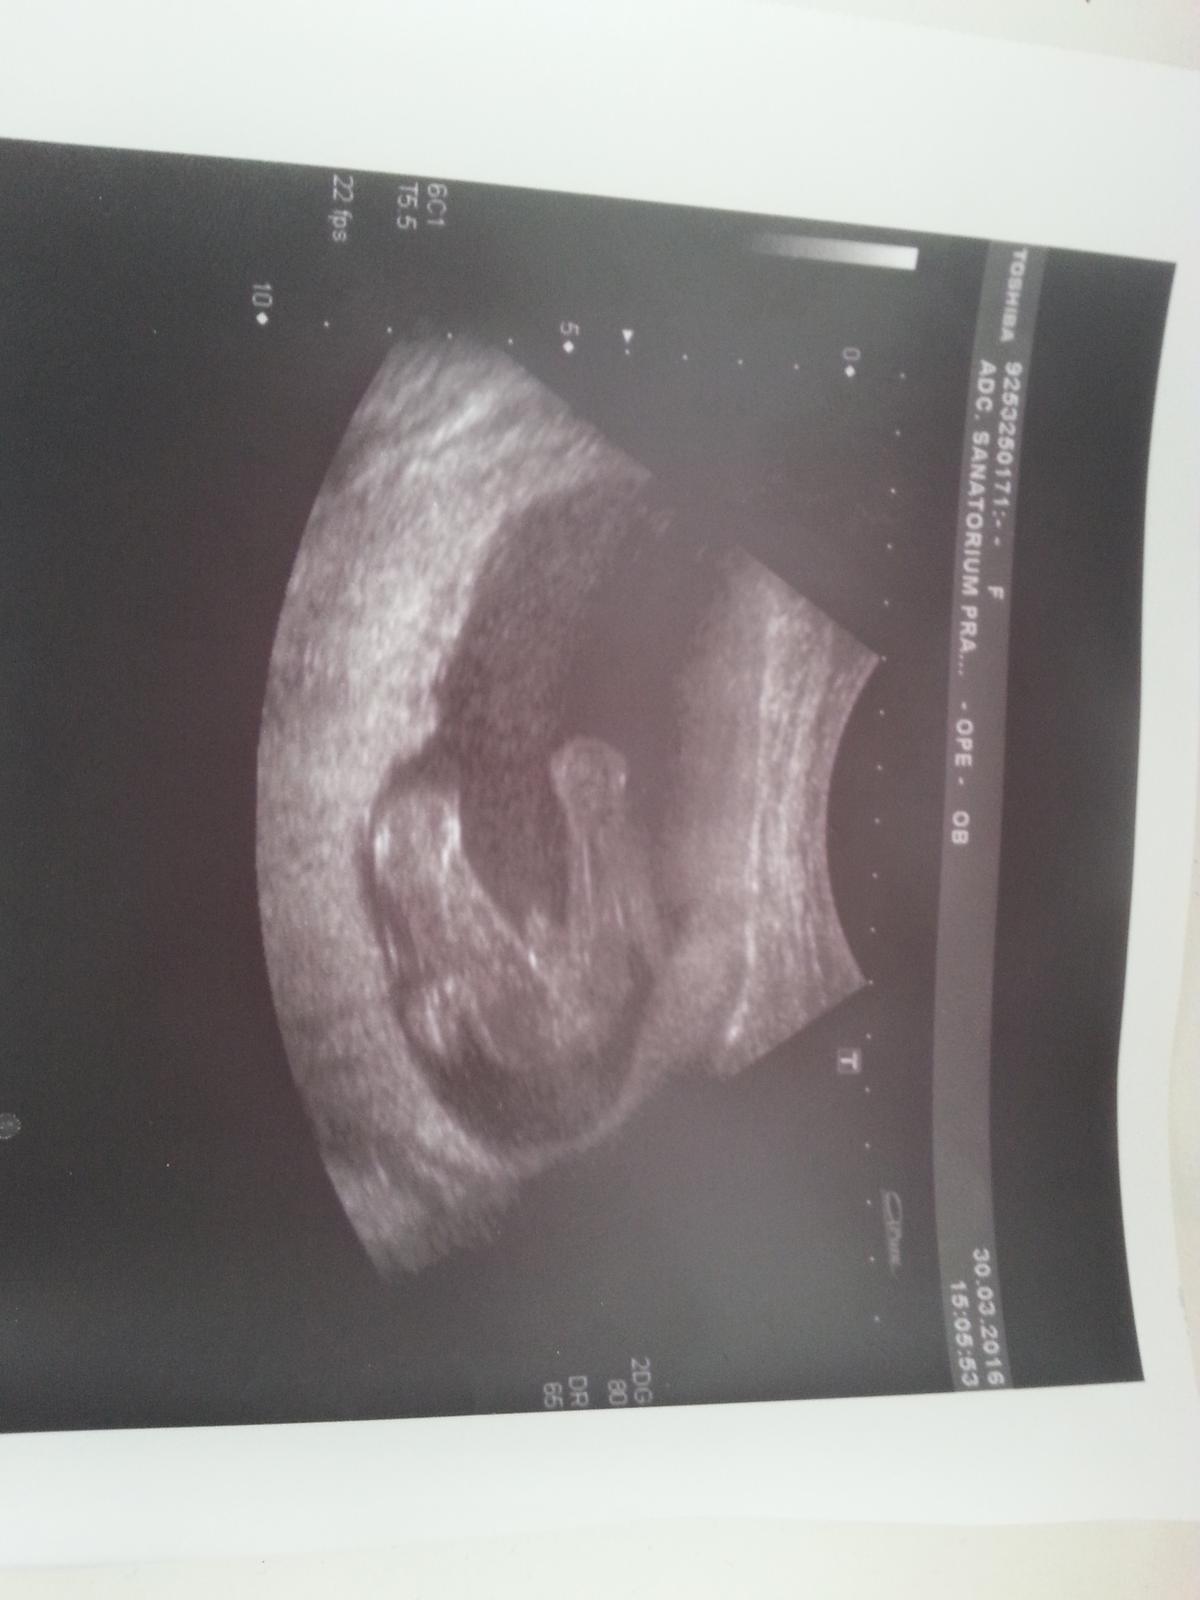

Je to holčička nebo chlapeček? Foto ultrazvuku

Tak dnes jsme se konečně dozvěděli co čekáme 🙂 Bude to holčička :-*

Holky moc gratuluji k holčičkám , máme potvrzeno ještě z 3D bude to opravdu malý fotbalista 🙂

Ahoj maminky,mam tady foto z utz ve 20tt. Co myslite,holka nebo kluk? 🙂 Ja svuj tip mam a zajima me nazor nekoho jineho 🙂